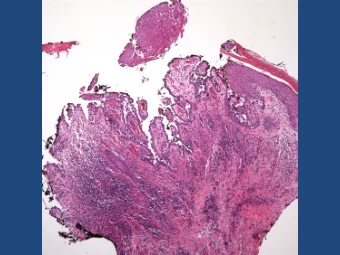

Stem Cell Differentiation in the Mouse Olfactory Epithelium

Cell Stem Cell, Fletcher et al, Deconstructing Olfactory Stem Cell Trajectories at Single Cell Resolution (2017)